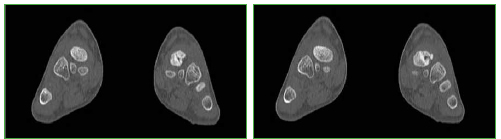

Tomografía computarizada con reconstrucción en plano coronal de ambos pies. Valorar comparativamente la morfología de ambos escafoides. El derecho es normal.

Tomografía computarizada, plano axial. Valorar comparativamente la morfología de ambos escafoides. El derecho es normal.